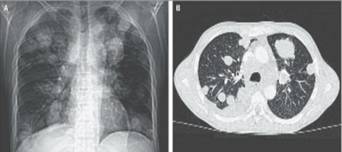

Theo CNN, giới y tế đã bắt đầu quan tâm hơn tới trường hợp ung thư hiếm có gây do bởi loài sán. Trường hợp của một người đàn ông 41 tuổi đã dấy lên những quan ngại mạnh mẽ hơn bao giờ hết về việc liệu nhiễm khuẩn thông thường có thể gây tử vong. Năm 2013, các bác sỹ ở Bệnh viện Medellin, Colombia đã tiếp nhận trường hợp một người đàn ông 41 tuổi bị mắc khối u đường kính 4cm trong phổi, tuyến thượng thận và hạch bạch huyết. Ông cũng dương tính với virus HIV nhưng lại không dùng thuốc chống HIV. Do vậy, hệ miễn dịch của người đàn ông này bị suy giảm nghiêm trọng. Sau quá trình xét nghiệm và đánh giá, các bác sỹ vô cùng ngạc nhiên khi nguyên nhân gây ra khối ung thư trong người bệnh lại không phải do vấn đề nội sinh. Nghiên cứu về chất liệu di truyền DNA tiết lộ, các tế bào gây ung thư đến từ một loài ký sinh trùng vốn dĩ thường ký sinh trong đường ruột của người có tên thường gọi sán dây lùn H. nana. Loại sán dây này thường được tìm thấy chủ yếu ở vùng khí hậu ấm áp và những nơi có điều kiện vệ sinh kém. Bệnh nhân 41 tuổi này không may đã chết sau đó vì suy thận. Tuy nhiên, các bác sỹ nghi ngờ rằng, các tế báo sán dây lùn là nguyên nhân chủ yếu gây ra cái chết cho bệnh nhân. Đây là trường hợp đầu tiên một bệnh nhân ung thư bị tử vong do tế bào đột biến trên ký sinh trùng gây ra. Điều này đặt ra những câu hỏi về hệ thống miễn dịch trong quá trình phòng ngừa và điều trị ung thư.

Các khối ung thư và hạch phát triển trong phổi, tuyến thượng thận và gan của bệnh nhân.